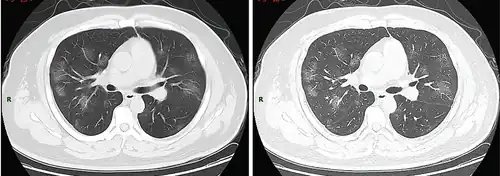

Dégâts pulmonaires

Les études en microscopie électronique et sur coupes histologiques de tissus pulmonaires (faites après autopsies) ont montré que les virions sont dans le poumon essentiellement localisés dans les pneumocytes[204].

Comme dans le cas du SARS, puis du MERS, la Covid se traduit dans l'arbre respiratoire par des lésions alvéolaires diffuses, caractérisées par des phases exsudatives et prolifératives de ces lésions, avec une congestion des vaisseaux capillaires et une nécrose systématique des pneumocytes, et très souvent une atteinte des membranes hyalines, un œdème interstitiel et intra-alvéolaire.

Les autopsies ont aussi révélé de fréquents événements thromboemboliques (« parfois cliniquement insoupçonnés au décès »)[205]. Outre une hyperplasie pneumocytaire de type 2, on a souvent observé une métaplasie squameuse avec atypie et micro-thrombus plaquettaire-fibrine[204],[206],[207],[208],[209].

L'infiltrat inflammatoire est toujours majoritairement composé de macrophages, souvent présents dans la lumière alvéolaire, souvent accompagnés de lymphocytes dans l'interstitium[204]. Des membranes hyalines se forment fréquemment, et une hyperplasie atypique des pneumocytes est également fréquemment constatée post-mortem. Le thrombus plaquettaire-fibrine des petits vaisseaux artériels peut être relié à une coagulopathie apparemment fréquente chez les malades de Covid-19 et qui selon Carsana & al (2020) devrait être l'une des principales cibles du traitement[204].